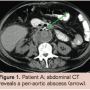

retroperitoneal abscesses (Figure 1). CT-guided puncture of only the periprosthetic hematoma was performed. The other abscesses were not punctured and drained. Culture revealed a Listeria monocytogenes. Although L monocytogenes infection is commonly seen in patients with close contact to milk and cheese products, our patient had no history of eating or working with these products. The graft infection was discovered 2 weeks after initial operation, and was considered an unfavorable period for a relaparotomy. We believed graft removal was not feasible in this patient because of his poor nutritional status, recent pneumonia and recent postoperative status. Therefore we started conservative treatment. Antibiotics were switched to amoxicillin and gentamicin, according to sensitivity of the cultured micro-organism and administered intravenously during 6 subsequent weeks. Control abdominal CT showed a reduction

of the abscesses (Figure 2). Blood levels of C-reactive protein (CRP) returned toward a normal value of 6 mg/L. The patient was discharged after a hospital stay of 61 days, with continuation of amoxicillin by mouth. An abdominal CT scan 15 months after discharge showed no signs of infection.